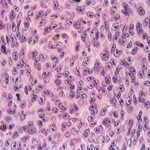

Cytological Features. The tumor cells in the dermis show great variation in size and shape. Nevertheless, two major types of cells can be recognized; an epithelioid and a spindle-shaped cell type. Many tumors show both types of cells, but usually one type predominates. Generally, the lentiginous forms of melanoma (e.g., LMM and ALM) tend to show a predominance of spindle-shaped cells in their invasive dermal components, whereas superficial spreading and nodular melanomas tend to be composed largely of epithelioid cells . The epithelioid type of cell tends to lie in alveolar or nested formations and the spindle-shaped type of cells in irregularly branching formations. The alveolar formations of the epithelioid cells are surrounded by thin fibers of collagen containing a few fibroblasts. Tumors in which spindle cells predominate may resemble sarcomas or other spindle cell tumors but in most cases differ from them by the presence of junctional melanocytic activity. |

The uniformly atypical nuclei of the cells that constitute the tumor nodule are larger than those of melanocytes or nevus cells, with irregular nuclear membranes, hyperchromatic chromatin, and, often, prominent nucleoli that tend to be irregular in size, shape, and number. The atypia is considered to be uniform if more than 50% of the cells have these |

characteristics, but more often than not, all or most of the cells are atypical. In addition to this uniform moderate or severe cytologic atypia, there is also a diagnostically important failure of the melanocytes in the deeper layers of the dermis to decrease in size (absence of maturation) . This must not be confused, however, with the presence of an intradermal nevus beneath a melanoma, a fairly common feature. Not uncommonly, melanoma cells will recapitulate nevic cell maturation (so-called pseudomaturation), but in these instances the smaller cells at the base retain nuclear characteristics of malignant cells, and there will be cytologic continuity between these nevoid cells and the overlying more atypical lesional cells. |